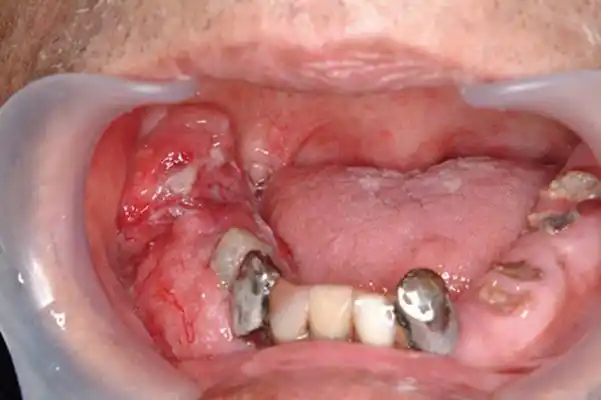

舌癌的初早期症状图片 (43)

轻微舌癌图片50

舌癌的初早期症状图片